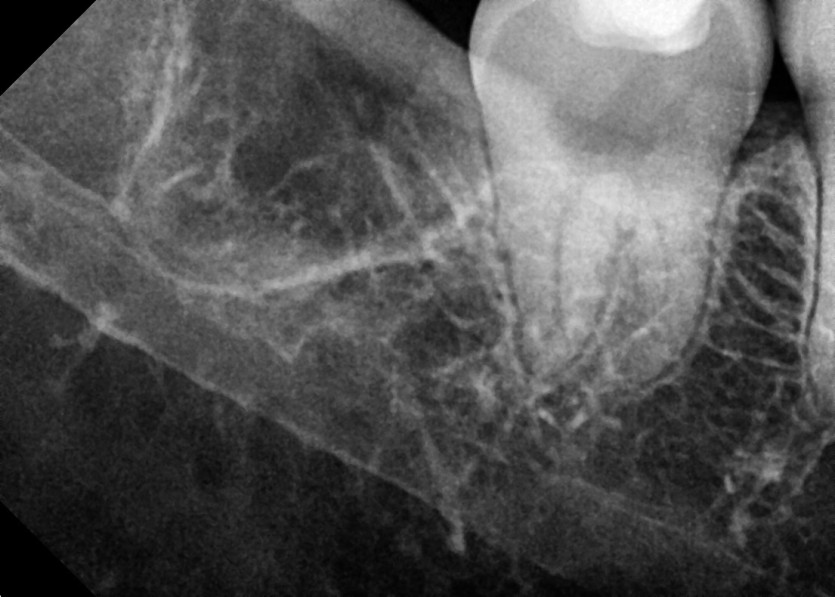

#38,48 사랑니 발치

구강 외과 전문의가 당일 발치했습니다.